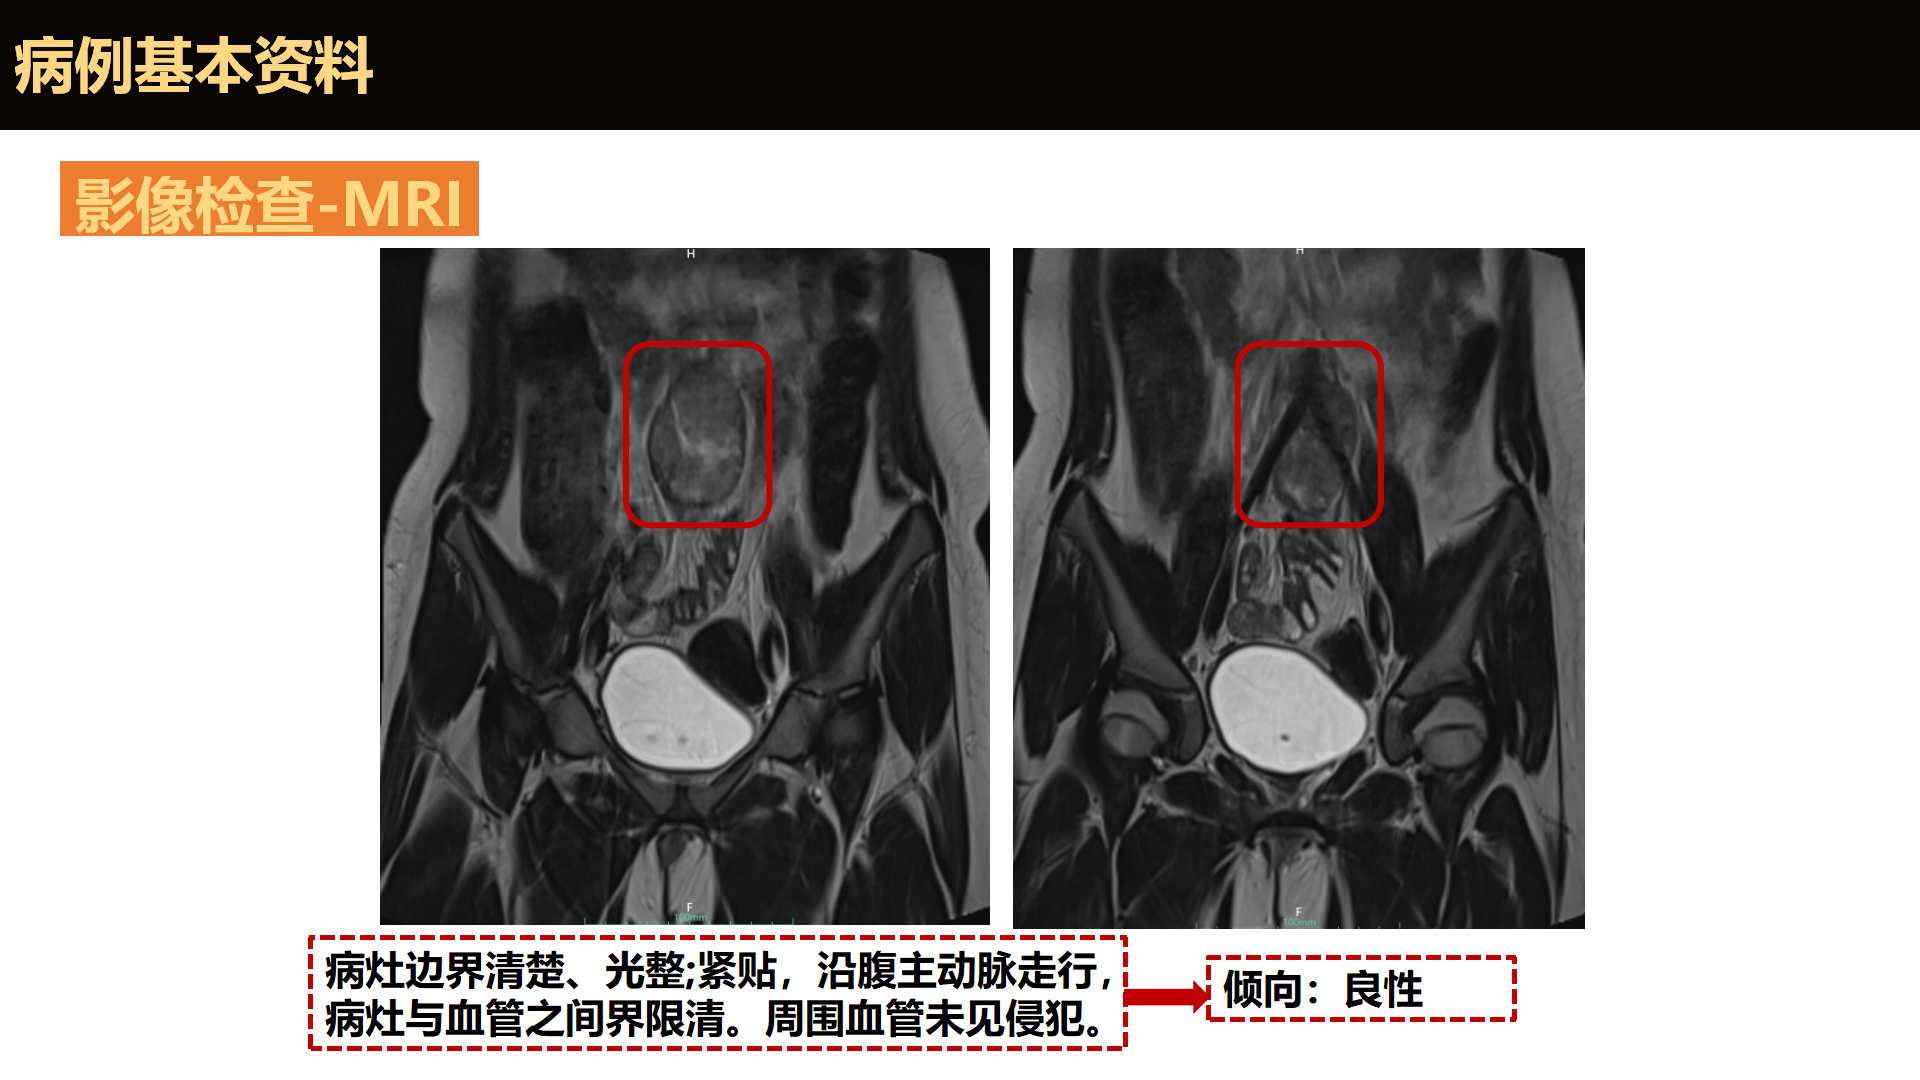

骇人的“高血压”——1例双侧嗜铬细胞瘤的诊治

“癌”影下的真相

3万皮肤科医师在看的年度大课——中国医学论坛报社“星火计划·最佳临床实践”重磅来袭!全国顶尖皮肤团队集结,Step by Step拆解疑难,直面真实临床战场!一个好病例,胜过千言理论;一次真解析,点亮诊疗明灯。今日奉上浙江大学医学院附属第二医院皮肤科满孝勇教授团队病例“‘癌’影下的真相”,反转再反转的诊疗过程,由陈希贝医生揭秘,满孝勇教授点评。 陈希贝 主治医师+关注皮肤性病科 | 浙江大学附属第二医院 满孝勇 主任医师+关注浙江大学附属第二医院 | 浙江大学附属第二医院